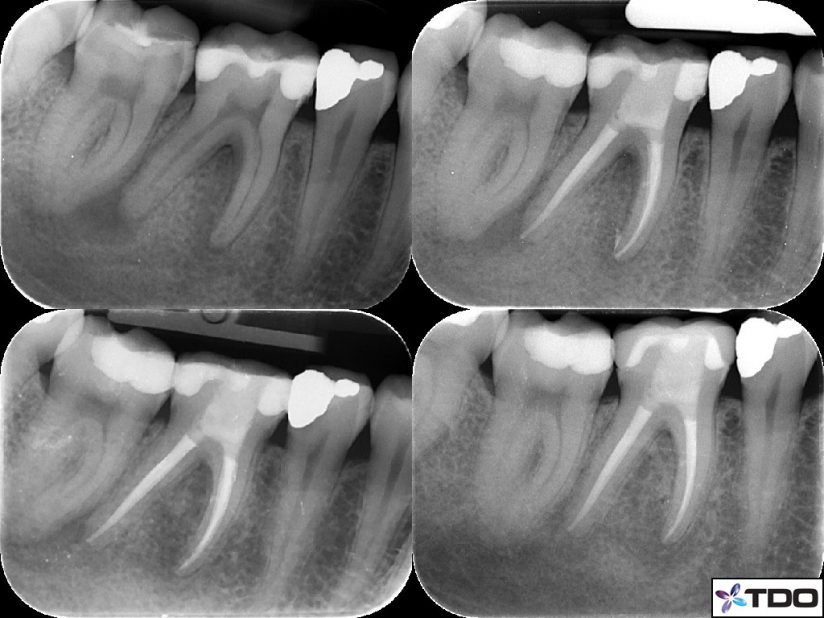

Patient A presented with necrotic pulp and a draining buccal dental abscess associated with tooth 46. Orthograde endodontic treatment was performed for the tooth over two visits with calcium hydroxide dressing.

Two weeks after debridement was completed Patient A was asymptomatic with the tooth and reported that the draining abscess associated with the tooth had ceased. The tooth was obturated with gutta percha and AH Plus sealer. A composite resin restoration of the access was completed.

At 6 months there is increased bone infill, and the tooth was recommended for rehabilitation with a crown.

At 12 months the crown has been placed by our referring dentist, and the tooth is asymotomatic and functional. Radipograph demonstrates near complete bone infill.